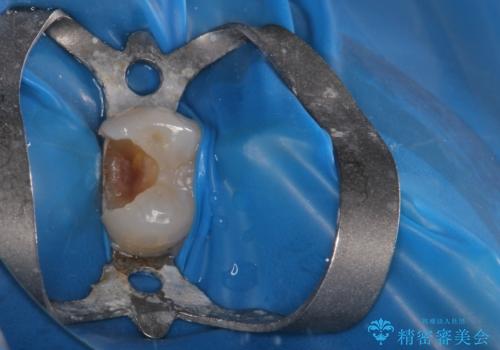

虫歯が神経に近接している可能性があるため、念のためラバーダムをして虫歯の除去を行いました。